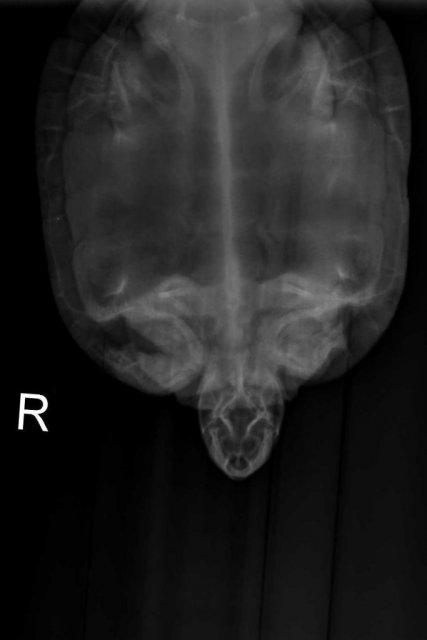

Алексей Alex-Raduga Ваше имя: Алексей Локация: Россия, МО, Серпуховский район Опубликовано: 29 марта 2024 Автор Опубликовано: 29 марта 2024 (изменено) @moth Есть рентген, она сначала долго пыталась вытащить лапку, снимок получился только одна кисть, потом снимала через панцирь. Вот оба снимка. Вообще она лапкой шевелит, даже плавала ей шевелила, кожа немного содрана только с пальцев. Рентген Тотоши не записали мне на флешку, я позвонил - должны прислать на E-mail, жду. Изменено 29 марта 2024 пользователем Алексей Alex-Raduga

Консультанты moth Ваше имя: Мария Локация: Москва Опубликовано: 30 марта 2024 Консультанты Опубликовано: 30 марта 2024 @Алексей Alex-Raduga Мария сказала перелома нет, ничего специального делать не нужно.